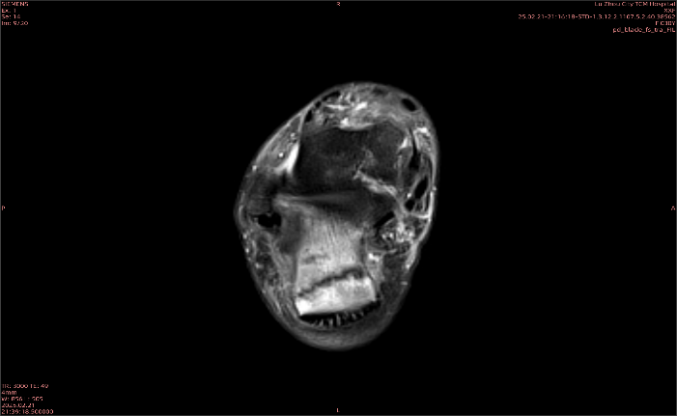

举例图像

图1

专业解释看不懂没关系,大家看图1和图2就可以了,这是同一个患者跟骨的磁共振和CT图像,图1的红色箭头指示的黑线就是磁共振图像显示的骨折线,一目了然。而对比图2的CT图像上并未显示异常。